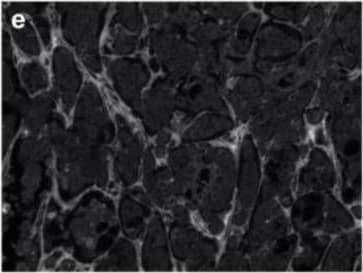

Detection of Human Tenascin C by Immunohistochemistry

Breast cancer brain metastases exhibit remodeled extracellular matrix. Non-cancerous control brain resections (a–c) and breast cancer brain metastases resections (d–f) were stained for collagen I (anti-collagen I), tenascin C (anti-tenascin C), and hyaluronan (hyaluronic acid binding protein). Representative images were selected across six patients (n = 6). Scale bar = 200 μm. Image collected and cropped by CiteAb from the following open publication (https://pubmed.ncbi.nlm.nih.gov/35200398), licensed under a CC-BY license. Not internally tested by R&D Systems.